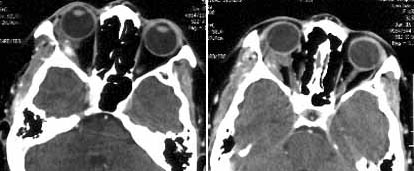

女性,35岁,右眼痛1周余,伴视物模糊,2年前有右眼出血史。

ct平扫,右眶内右下象限、外直肌外见团块状肿物,内散在结节状钙化。

增强扫描,肿物内可见明显强化的血管影。

ct诊断:右眶内海绵状血管瘤。